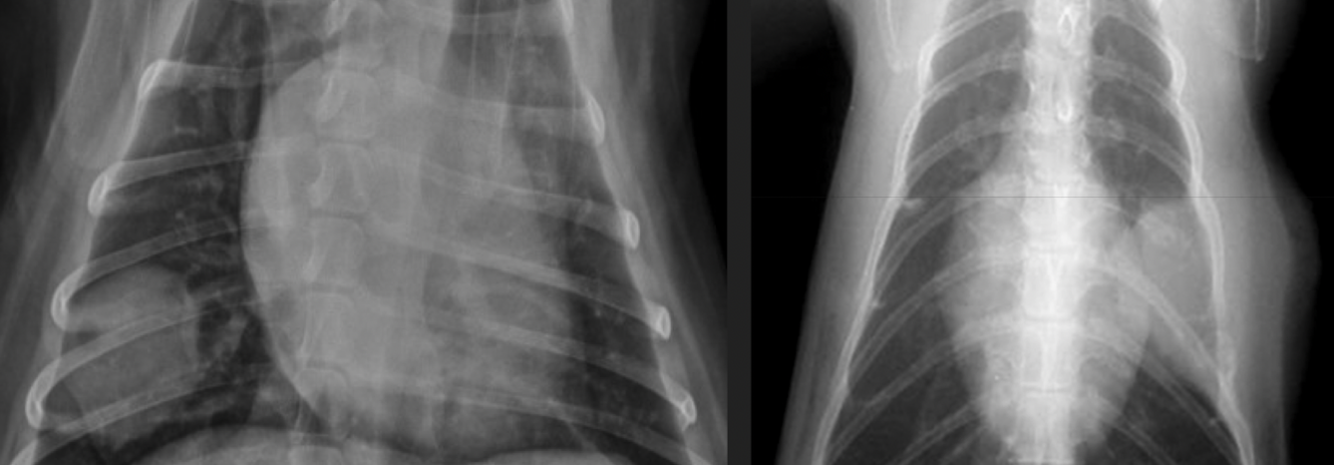

25

where are lymphnodes in this pt with medistinal lymphadenopathy

26

what is happening? ddx

cranial mediastinal mass- pushing everything **Thymus** →Neoplasia (Thymoma, Lymphoma); [↓Hemorrhage] **Lymph node** (sternal, cranial mediastinal)→ Neoplasia (Lymphoma) **Mediastinum / Adnexa** →Neoplasia (Sarcoma, Carcinoma); Cyst; [↓ Abscess, Granuloma, Hemorrhage]